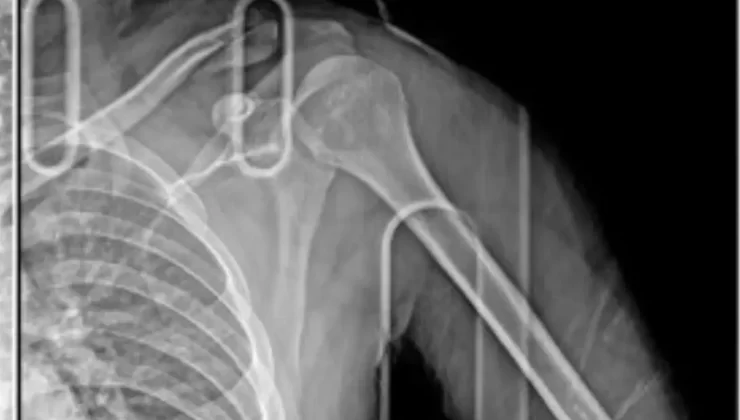

Olay, 11 Kasım Pazartesi günü saat 22.00 sıralarında Bahçeşehir-Esenkent yolunda meydana geldi. Teze nazaran, şoförünün Y.Y olduğu öğrenilen 34 EMN 030 plakalı araba, siparişi teslim ettikten sonra restorana dönüş yapan kurye Yakup Çiçek’in kullandığı motosiklete arttan çarparak kaçtı. Yakup Çiçek, motosikletten savrularak yaralanırken, araba şoförü durmadan kaçtı. Etraftakilerin ihbarı üzerine olay yerine sıhhat ve polis takımı sevk edildi. Çiçek, yaralı halde hastaneye kaldırılırken, sağ omzundan ameliyat oldu. Çiçek’in platin takılan kolunda kalıcı hasar oluştu. Hastanedeki tedavisinin akabinde meskeninde istirahate çekilen Çiçek, işine devam edemeyeceğini tabir ederek, adaletin yerini bulmasını istedi. Çiçek, araba şoförü Y.Y.’den şikayetçi oldu.

Vücudunda kazanın izlerini taşıyan Yakup Çiçek, “11 Kasım’da akşam saat 22.00 sıralarında, lüks bir araç ana cadde üzerinde giderken çapraz bir halde bana vurdu. Vurduğu sırada motorum pert oldu, bana vuran da kaçıp gitti. Kuryelik yaptığım için paket bırakmıştım, paketten restorana dönüyordum. Dönerken bu kaza gerçekleşti. Gerçekleştikten sonra bana vurdu ve sanırım bir dakika beklemedi bile, direkt kaçıp gitmiş. O sırada, ben esasen yerde baygın bir haldeyim. Gözlerimi ambulansta açtım. Gözlerimi açtıktan sonra beşerler yanaştı, bu kişinin aslında daha evvelce vukuatları olduğundan bahsettiler. Ben de aslında o mevkide onu görüyordum. Zira kaplamalı bir araçtı. Şu an hala süreçler devam ediyor. Şu an koluma platin takıldı ve ömür uzunluğu kalacak. İşimden oldum, motorum pert oldu. Motorum kullanılmayacak halde. O formda benim de 3-4 ay yatışım var. Sigortadan bir şey alamayacağım, benim çalıştığım yer buna müsait değil. Raporum hiçbir formda geçerli değil. Maddi ve manevi her açıdan beni güç duruma soktu ve hala rahat bir biçimde geziyor. Rahat bir formda paylaşımlar atıyor, görüyorum. Hiçbir şey yapılmıyor” dedi.

Araba şoförünün daha evvel misal kazalar yaptığını öğrendiğini belirten Çiçek, “Çevredekiler ihbarda bulundular, etraftakiler bana çarpan kişiyi tanıdıklarını ve daima vukuatta bulunduğunu söylediler. Zati plakayı bile etraftakilerden öğrendik. Bana çarptığı sırada farları kapalıydı çocuğun bu ortada. Farları yoktu. Sağ farı da çatlamış bana vurduktan sonra. Bana çaptığı anda motorum aşağı yanlışsız, ben de üst yanlışsız zıpladım, 5-6 takla attım. Düştüğümde baş üstü düştüm, şuramdan bir kırık aldım. 2-3 takla daha attım. Motorum zati, 6-7 modüle bölünmüştür. Orada aslında toparladılar” sözlerini kullandı.